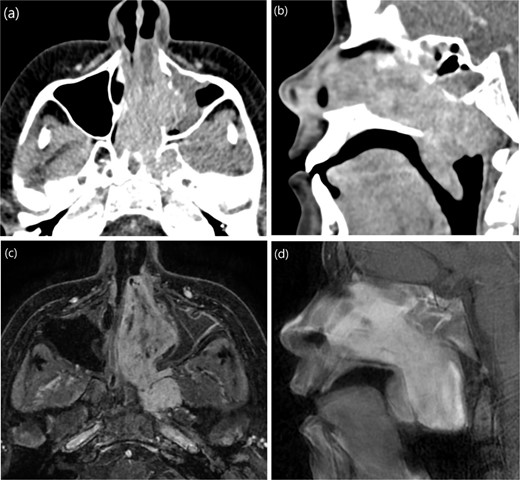

Case 4: Extreme lateral infratemporal fossa extension

A 13-year-old male presented to the hospital with a two-year history of gradually worsening obstructive symptoms. Endoscopic examination revealed a pale, necrotic mass in the left inferior nasal cavity, along with severe septal deviation and bilateral nasal discharge. CT and T1-weighted MRI identified a mass in the left nasal cavity extending posteriorly into the nasopharynx, laterally into the maxillary antrum and left pterygopalatine fossa, and posteroinferiorly into the oropharynx (Fig. 4). The patient underwent preoperative embolization of the branches of the left external carotid artery (ECA), followed by navigation-assisted endoscopic surgical excision (Fig. 5).

(a, b) Contrast-enhanced CT of the paranasal sinuses in transaxial and sagittal views showing a mass in the left nasal cavity with extension into the nasopharynx. (c, d) Post-contrast T1-weighted MRI in axial and sagittal views illustrating the mass extending laterally into the maxillary antrum and left pterygopalatine fossa, as well as posteroinferiorly into the oropharynx.

The excision was extended laterally to the boundaries of the left infratemporal fossa (Fig. 6). The patient was discharged in stable condition the following day. However, one week later, the patient developed left-sided otalgia, tinnitus, left-sided headache, and clear nasal discharge without any bleeding or obstruction. Five weeks later, he experienced decreased visual acuity in the left eye. Examination revealed a fleshy mass in the pterygopalatine area with purulent discharge, necessitating revision endoscopic excision.